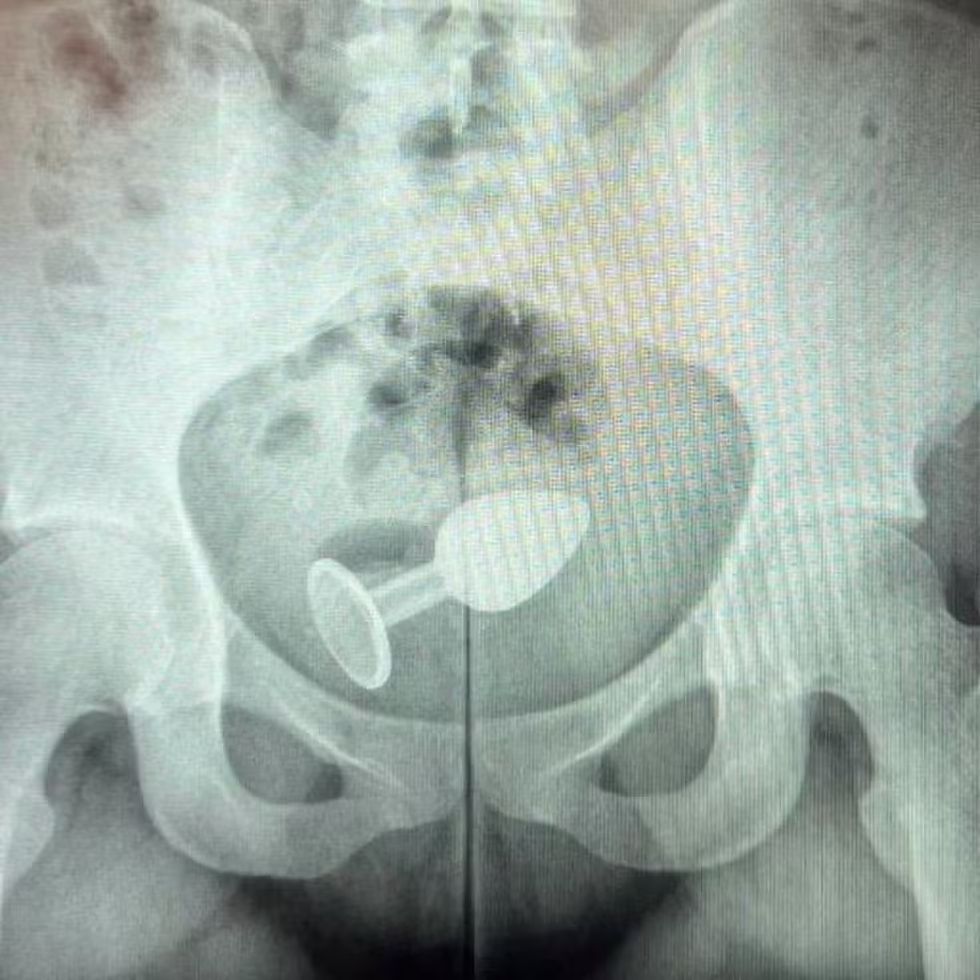

No vídeo mais recente, ele mostra o raio-x de uma paciente que estava usando um plug anal que subiu para o reto e ela não conseguiu mais tirar. Ela precisou ser hospitalizada para a retirada.

Segundo o especialista, no caso da paciente do vídeo, a “empolgação” durante o sexo acabou fazendo com que o objeto subisse para o reto, tornando impossível removê-lo sem intervenção médica.